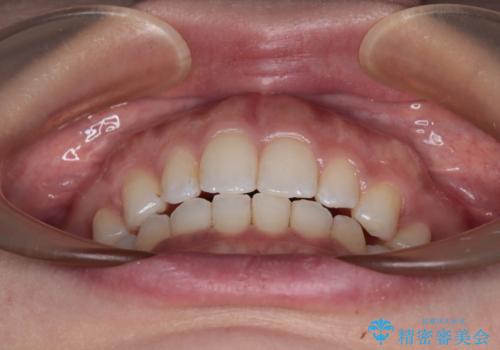

- 唇が閉じにくく、上の前歯が下唇に当たって気になるとのことで来院された患者様です。

レントゲン写真での分析結果からは、抜歯矯正をするかどうか悩む境界線上でしたが、主訴が口元の突出感であったため、上下左右の第一小臼歯4本を抜歯して矯正治療を行うこととしました。

上下ともに前歯が少し舌側に傾斜したような仕上がりとなりましたが、口が閉じやすくなったとのことで、患者様には大変満足していただけました。